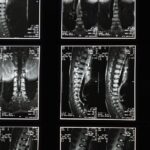

- Comprehensive Initial Evaluation: A thorough assessment including advanced imaging (MRI, CT scans), neurological evaluation, and detailed clinical history establishes the spinal condition’s nature and severity. Dr. Desforges’ extensive osteopathic and naturopathic qualifications contribute to a holistic diagnostic approach.